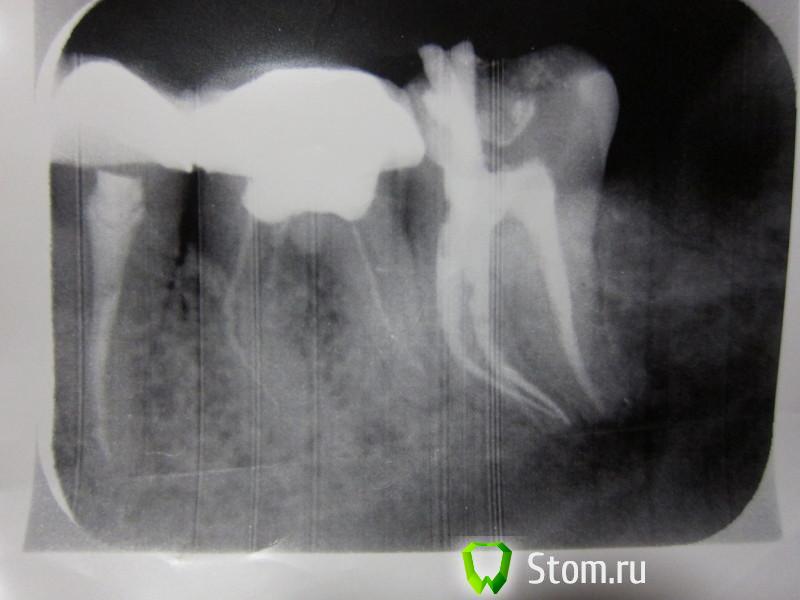

Людмила Рогозина Опубликовано 21 марта, 2012 Поделиться Опубликовано 21 марта, 2012 Помогите, нужна срочная консультация. На 37 зубе обнаружили гранулёму. История этой проблемы вкратце: в августе 2011 заболел 37 зуб - пульпит под старой пломбой - пролечили. На первых снимках никакого намёка на гранулёму! Через неделю планово удалили дистопированную ретинированную "восьмёрку" рядом - чтоб не давила на свежепролеченный зуб. Для профилактики пила линкомицин.Боли никак не проходили, при накусывании зуб сильно болел, через 5-6 недель вернулась к своему стоматологу, сделали снимок, обнаружили это затемнение поставили диагноз "периодонтит". Лечили: распломбировка, депофорез 3 раза, неделю с метапексом, затем новая пломбировка, 10 дарсонвалей, боли не утихают - инъекция преднизолона в складку, затем курс амоксиклава. Боли чуть отпустили. Первый снимок от 20 октября - сразу после перелечивания. После сняли коронку с соседнего 36, т.к. она давила на больной зуб. Через 3 месяца решила покрыть 36 зуб опять коронкой, но его перелечить не смогли, лет 15 этот "вусмерть зарезорциненный" (выражение моего врача) зуб с пустыми каналами стоял под коронкой, там каналы "застекленели". К тому же в одном из каналов там обнаружили давнишний отломок инструмента - достать, естественно, не смогли - они непроходимые вообще. Но один канал слегка расширили и установили туда анкерный штифт. Второй снимок от 3 февраля 2012 как раз по этой теме. На простых снимках врачи не видели гранулёму, говорили, что периодонтит, только на КТ обнаружили - 20 февраля. КТ выкладывать не буду, там ужасное качество, всё мелко, диска не дали, только мутные негативы, могу выложить описание (делали в ЦНИИСе - я в шоке от "качества" услуги). Суть в том, что "апикальная гранулёма визуализируется у верхушки медиально-язычного корня 37 зуба, а у 36 - разрежение костной ткани". Ортопед сказал: раз 36 перелечить не смогли - коронкой покрывать не буду. А если на 37 гранулёма, то и жалеть нечего, оба одновременно удалять и ставить импланты. С ним согласны не все специалисты. На комиссии мнения врачей разделились. Кто-то настаивал, что за гранулёмой нужно ещё минимум полгода понаблюдать, посмотреть динамику, а 36 закрыть коронкой и, когда заболит (может, даже лет через 10), удалить вместе с коронкой. 36 зуб не болит вообще и никогда не болел. 37 слегка чувствителен при прикосновении, но это не боль, а какое-то легкое "зудение", жую на нём спокойно, даже жёсткую пищу, "постанывают" иногда окружающие зуб ткани и кость под ним (или это так дырка от "восьмёрки" так заживает, не могу понять). К стоматоневрологу в МГМСУ ходила, воспаление тройничного нерва мне исключили.С хирургом тоже консультировалась - он не хочет делать резекцию, т.к. там очень близко расположен челюстной канал, опасается пареза. В гемисекции нет смысла - лучше имплантация. Реплантация - вообще экзотика. Помогите, что делать?! Можно ли попробовать под микроскопом перелечить эти несчастные 36-37 зубы в третий раз?! Или найти более смелого хирурга? Есть ли смысл в "наблюдении" за гранулёмой, вдруг начнутся осложнения? И что это за затемнение на втором снимке внизу на челюсти? На КТ мне его проигнорировали. Заранее спасибо. Ссылка на комментарий

ger_berra Опубликовано 28 марта, 2012 Поделиться Опубликовано 28 марта, 2012 Спасибо большое за ответ!Затемнение, мне кажется, на кости челюсти. Или это такой визуальный эффект от "закругления"?Иногда чувствую там какие-то давящие боли в (районе сустава).Перелечивание под микроскопом - 25 тыс один зуб и без гарантий... Может быть, проще чуть-чуть добавить и импланты поставить? (хотя там тоже без гарантий!)Могли ли на КТ "просмотреть" перфорацию и кусок инструмента? И способен ли микроскоп справиться с "застекленелостью" и "непроходимостью" каналов?Это канал,в котором нижнечелюстной нерв находится.Лучше попытаться сохранить свой зуб,хотя у Вас не из простых. Микроскоп сам по себе не борется с непроходимостью каналов.Это лишь девайс.Если доктор не обладает необходимыми знаниями и навыками,то никакая оптика не поможет. Ссылка на комментарий